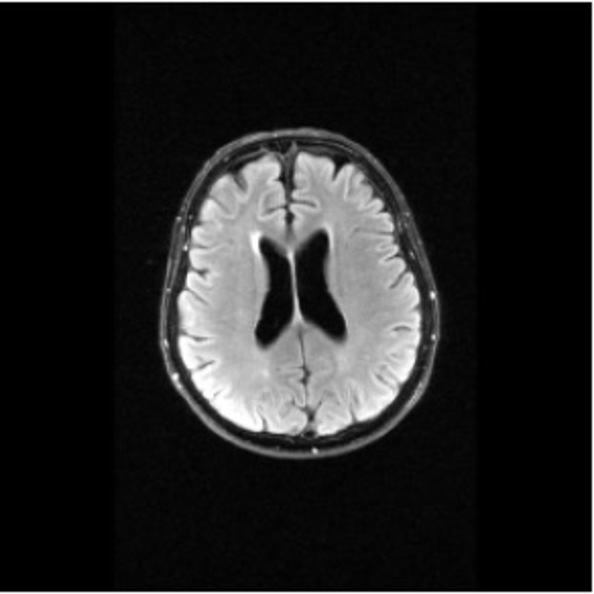

Figure 2: Example MRI magnitude reconstructions with S=25S=25 training slices at acceleration factor R=7R=7. PaDIS-MRI reconstructions are sharper and more faithful to the fully-sampled ground truth. Insets are shown to highlight detail.

Figure 2 provides a visual comparison of the reconstruction quality of each method on example slices. In reconstructions from the S=25,R=7S=25,R=7 models, FastMRI-EDM exhibits slightly more blurring and loss of fine structural details, particularly in regions with complex anatomical features. PaDIS-MRI, in contrast, preserves sharper boundaries and finer details. This enhanced data efficiency can be attributed to the patch-based prior’s ability to learn localized structural motifs more effectively from limited examples. Figure 6 in the Appendix shows similar reconstructions at S=200,R=7S=200,R=7 where FastMRI-EDM more closely approaches the performance of PaDIS-MRI but still struggles with highly detailed anatomy. At both dataset sizes, MoDL underperforms the diffusion priors. In Figure 2, MoDL’s FLAIR reconstruction exhibits pronounced artifacts, likely reflecting reduced generalizability of a supervised prior when the training distribution underrepresents FLAIR.